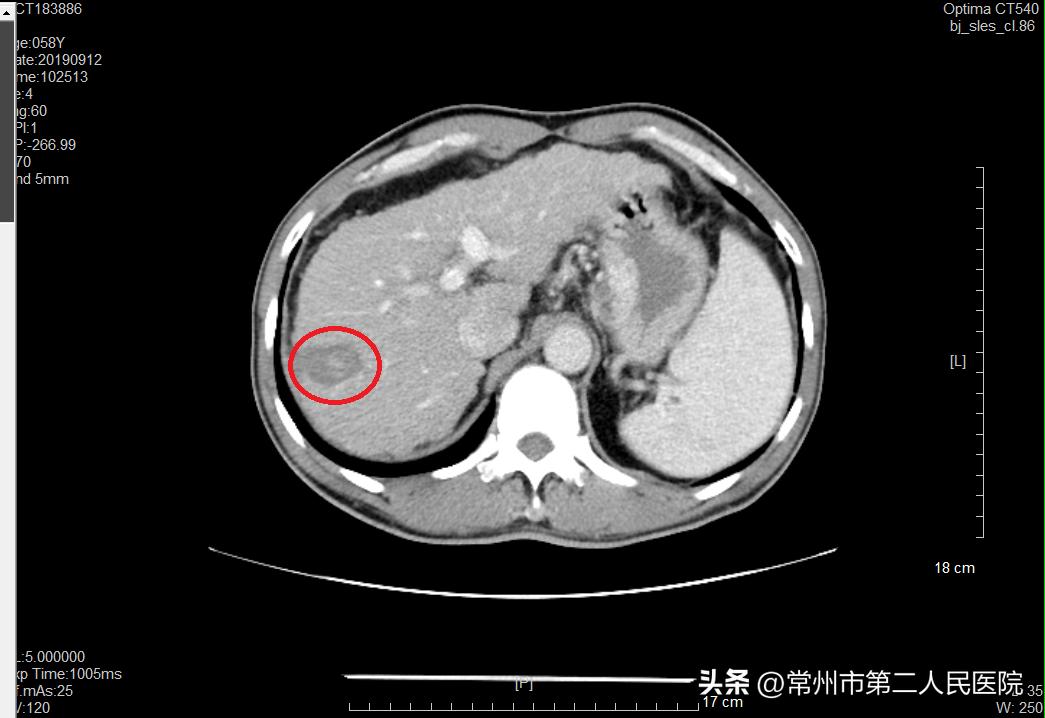

▲术后肿瘤完全坏死,留下包含坏死组织的软化灶

“像姚先生这样的病例,过去治疗方法包括肝切除术、全身静脉化疗,现在介入治疗成为部分肝癌首选治疗方法。治疗过程中,我们将一根铅笔芯粗细的消融针,在CT引导下穿刺入肿瘤内,外接消融治疗仪,以90℃以上的温度直接将肿瘤组织碳化灭活。治疗5cm以内的原发性肺癌、原发性肝癌可达到与手术切除相当的治疗效果;对于肺、肝转移性癌进行部分或完全灭活可起到减轻患者肿瘤负荷、延长生存时间、提高生活质量的效果。由于治疗时间短,患者的损伤小,术后2-3天就可以出院恢复正常生活。”